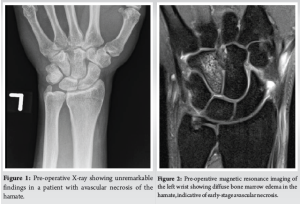

Initial radiographs were unremarkable (Fig. 1), consistent with early-stage AVN. MRI revealed diffuse bone marrow edema within the hamate, consistent with AVN (Fig. 2). No associated fractures or significant degenerative changes were noted. In addition, there was no evidence of tendon abnormalities or pathology at insertion sites. Gadolinium-enhanced imaging was not utilized in this case, though its use remains at the clinician’s discretion, as there is no established gold standard in the literature regarding its necessity for diagnosing hamate AVN.